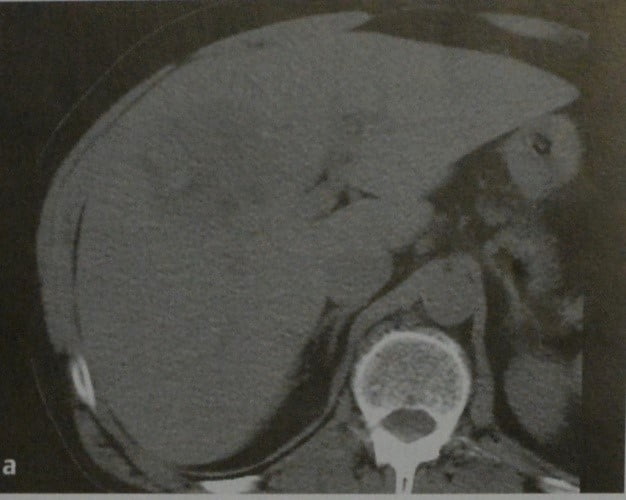

Методы динамического контрастирования печени на МРТ

Раздел: Снимки-подсказки